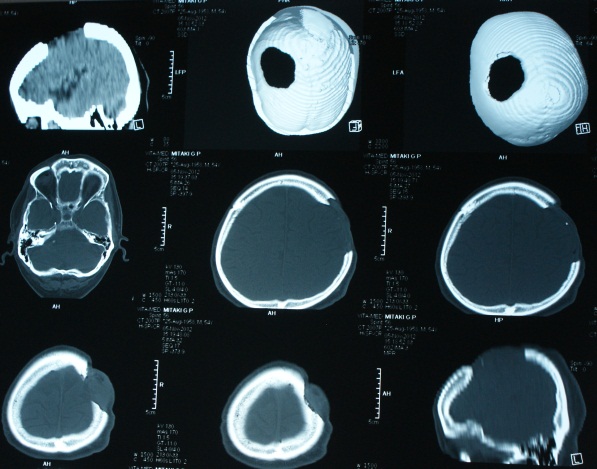

Дефекты костей свода черепа

• Дефекты костей свода черепа возникают после травм, оперативных вмешательств.

• Краниопластика – операция, направленная на закрытие дефектов костей свода черепа.

Для закрытия костных дефектов могут использоваться различные материалы:

> аутокость;

> титановые сетки;

> полимерные материалы;

> и др.

Мы выполняем краниопластики с использованием современных материалов.